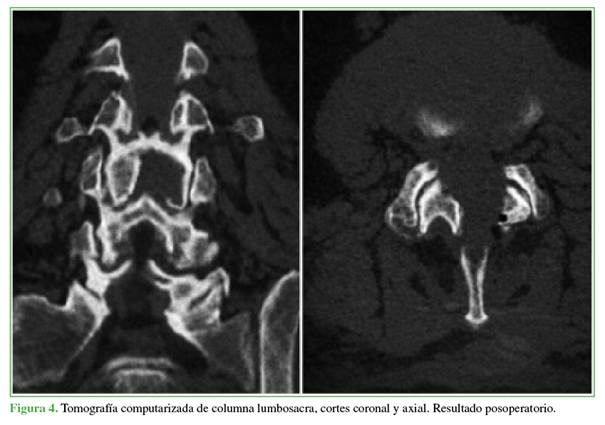

Los hallazgos fueron consistentes con un quiste sinovial facetario hemorrágico. Dados la presentación aguda con déficit neurológico motor progresivo y el severo compromiso radicular, el paciente fue sometido de urgencia a una descompresión. El objetivo fue aliviar la compresión neural, revertir el déficit motor y permitir una recuperación funcional rápida, minimizando la invasividad. Se optó por una descompresión endoscópica uniportal interlaminar posterior, utilizando un abordaje contralateral (izquierdo) y la técnica “over the top” (por encima del saco dural) para resecar el quiste de forma segura y completa (Figuras 2-5).

El procedimiento duró 95 min, la pérdida sanguínea fue mínima, no cuantificable y no se produjeron complicaciones intraoperatorias.

El paciente tuvo una evolución posoperatoria inmediata favorable. En las primeras 24 h, el dolor mejoró notablemente (2/10 en la escala analógica visual) y la recuperación motora era incipiente. Fue dado de alta a las 24 h con un plan de rehabilitación kinésica ambulatoria. En el control a los 7 días, la fuerza en la flexión dorsal de los tobillos había mejorado a 5/5.